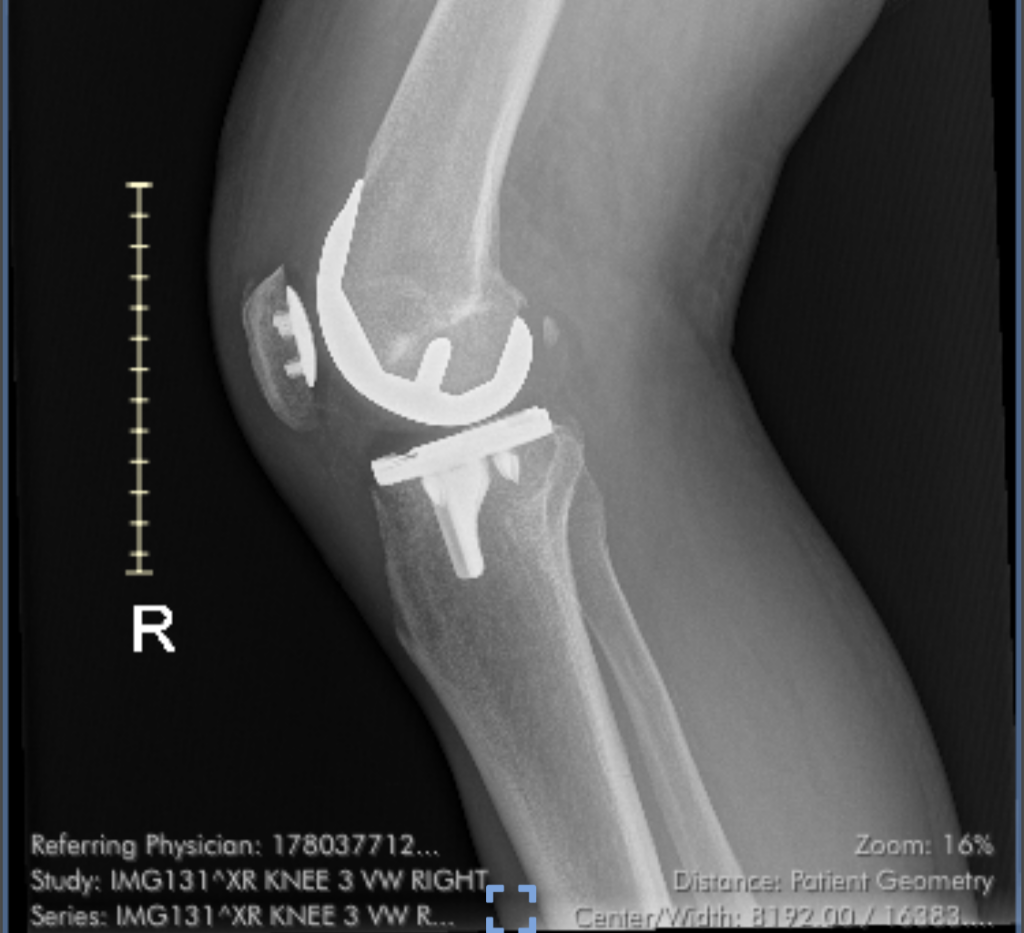

First known photo of my new knee. The day after surgery.

But running ended completely in late 2023, and after a year of limping, I had the offending joint replaced in December 2024. Rehabilitation went extraordinarily well thanks to my physical therapist, Paul, the Knee Whisperer, who knew I wanted to hike the Grand Canyon and pushed me hard and successfully to recover. Two months after surgery, I was surfing the Grand Canyon R2R Facebook page, swapping questions and concerns with other knee replacement old timers, hoping to hike the canyon. Those people could not have been more helpful and inspirational. Some had both knees replaced and were all in!